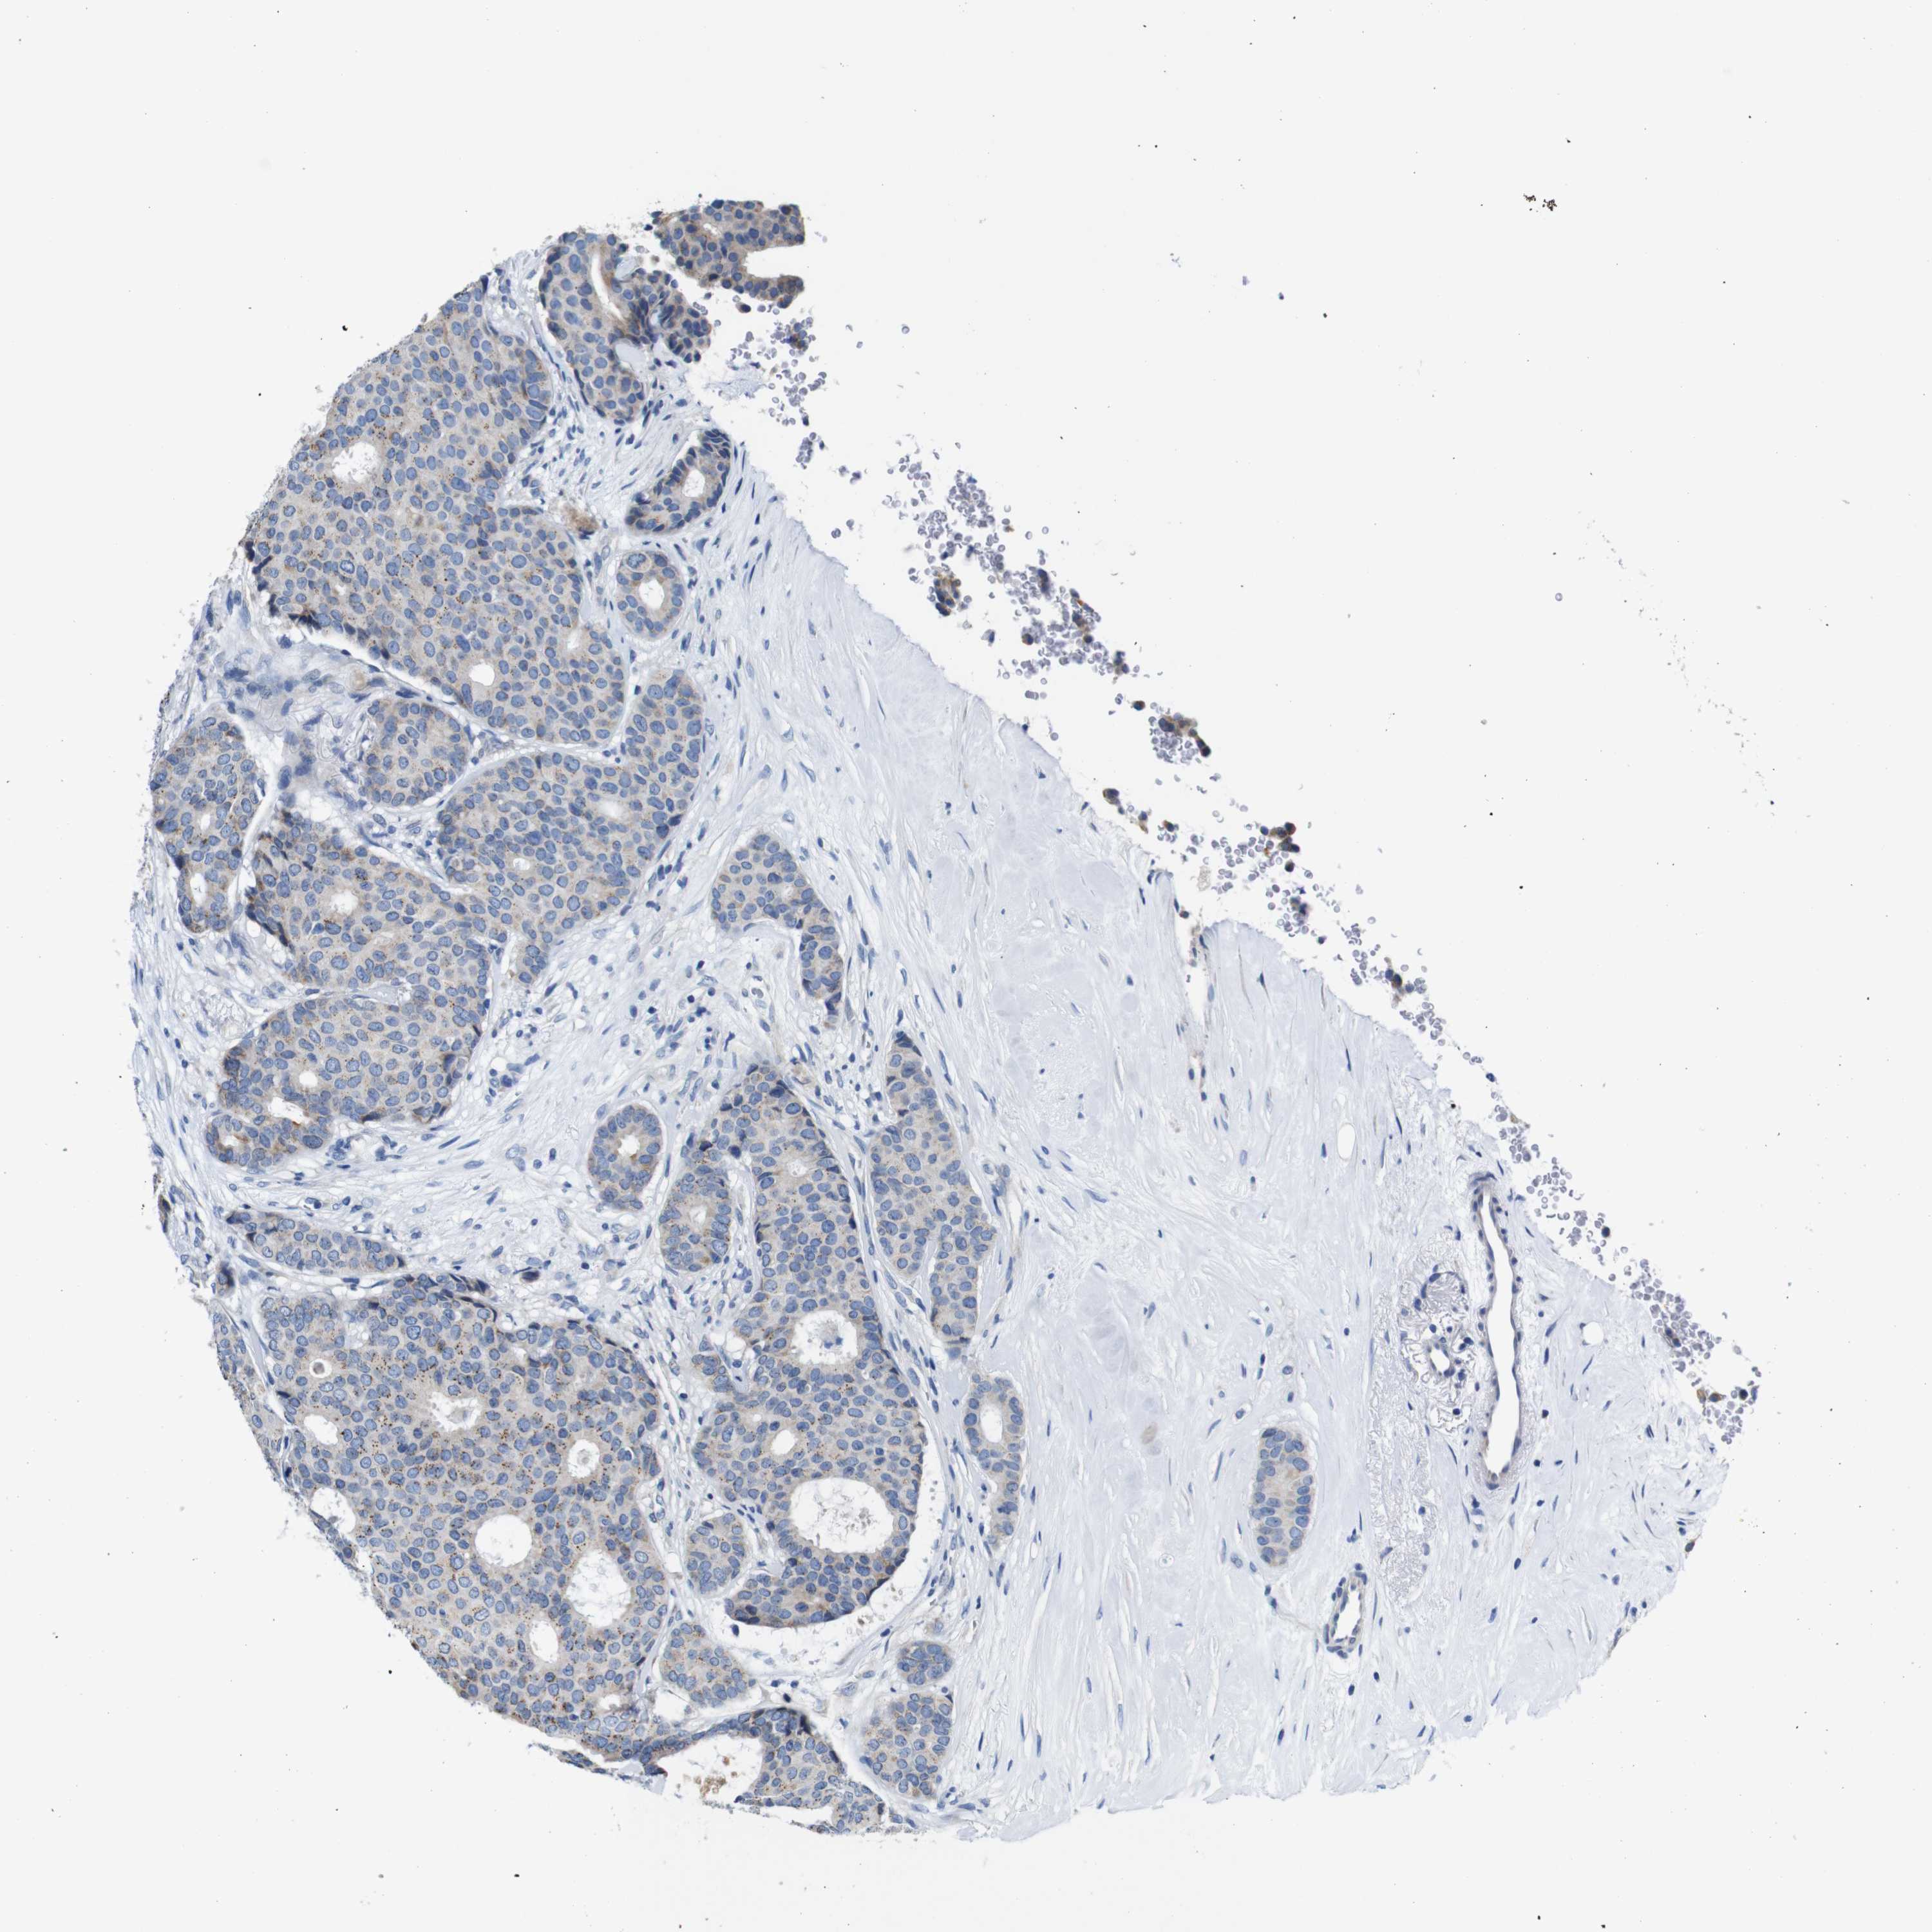

CANCER BREAST CANCER Show tissue menu

BRCA TCGA BRCA VALIDATION PROTEIN EXPRESSION

Breast cancer

Human cancer